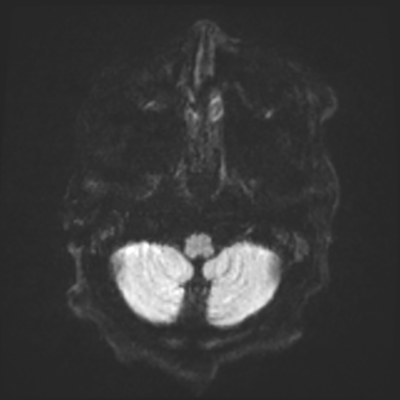

You come back the next day and see how things are going. The patient's electrographic record has shown a moderate encephalopathy (diffuse slowing, disorganization) with frequent right posterior quadrant delta slowing. Based on this result, and an adequately improved clinical examination, you give the okay to proceed with obtaining an MRI of his brain. This is shown below.

MRI brain (DWI)